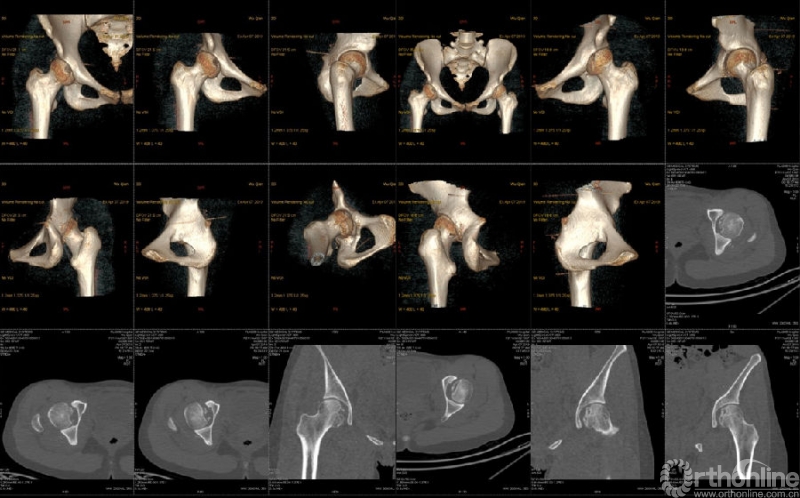

骨盆CT示:双髋关节后脱位伴双股骨头骨折。

影像学检查